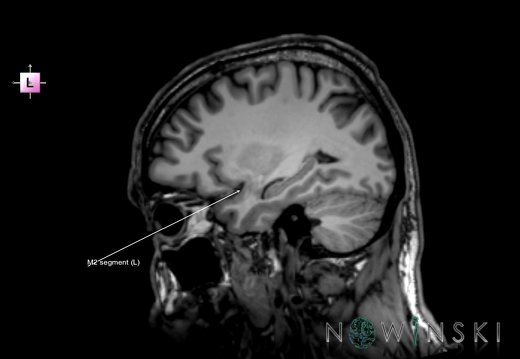

G6.T15.2.V2.P20S.Intracranial arteries–Triplanar